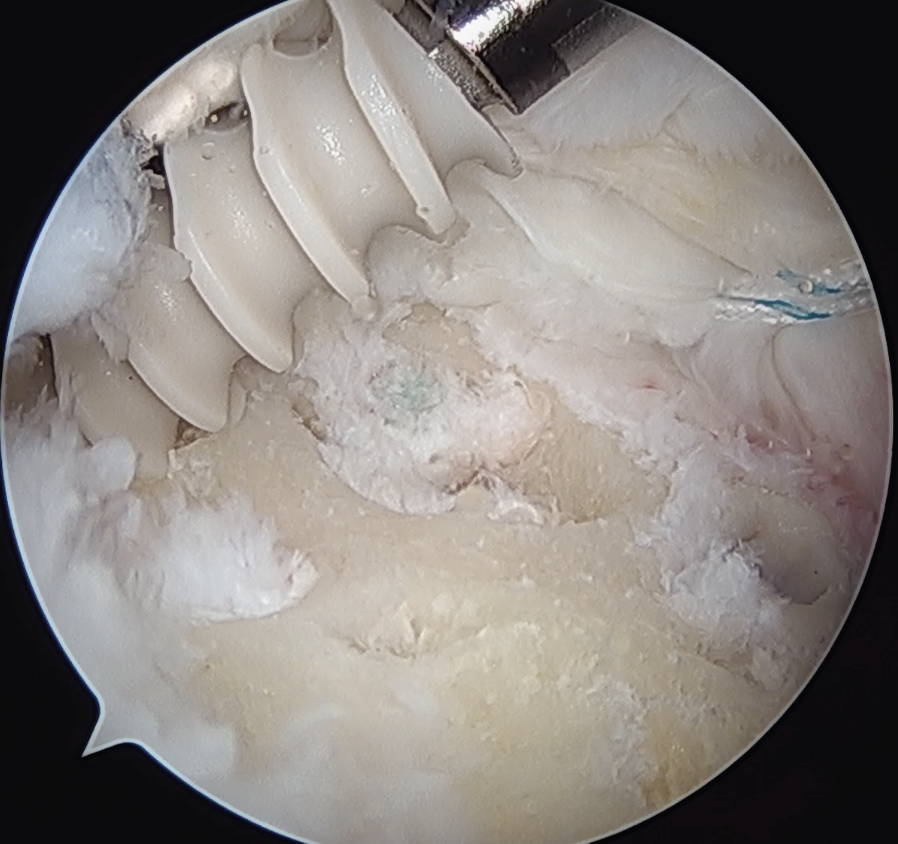

Subacromial joint

- bursectomy for visualization

- acromioplasty if acromial spur

- debride footprint to bleeding bone

- +/- microfracture / K wire of footprint / marrow stimulation

Arthroscopic Cuff Tearcuff

Assess tear

- large tears may need releases